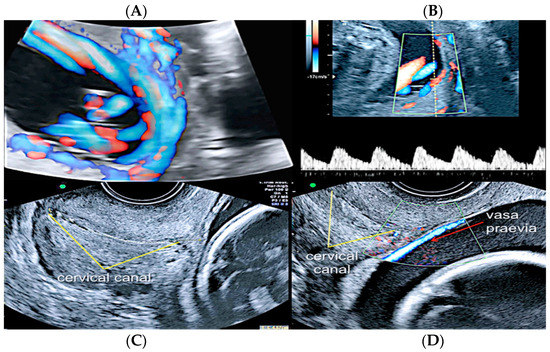

3.2.2. Vasa Praevia